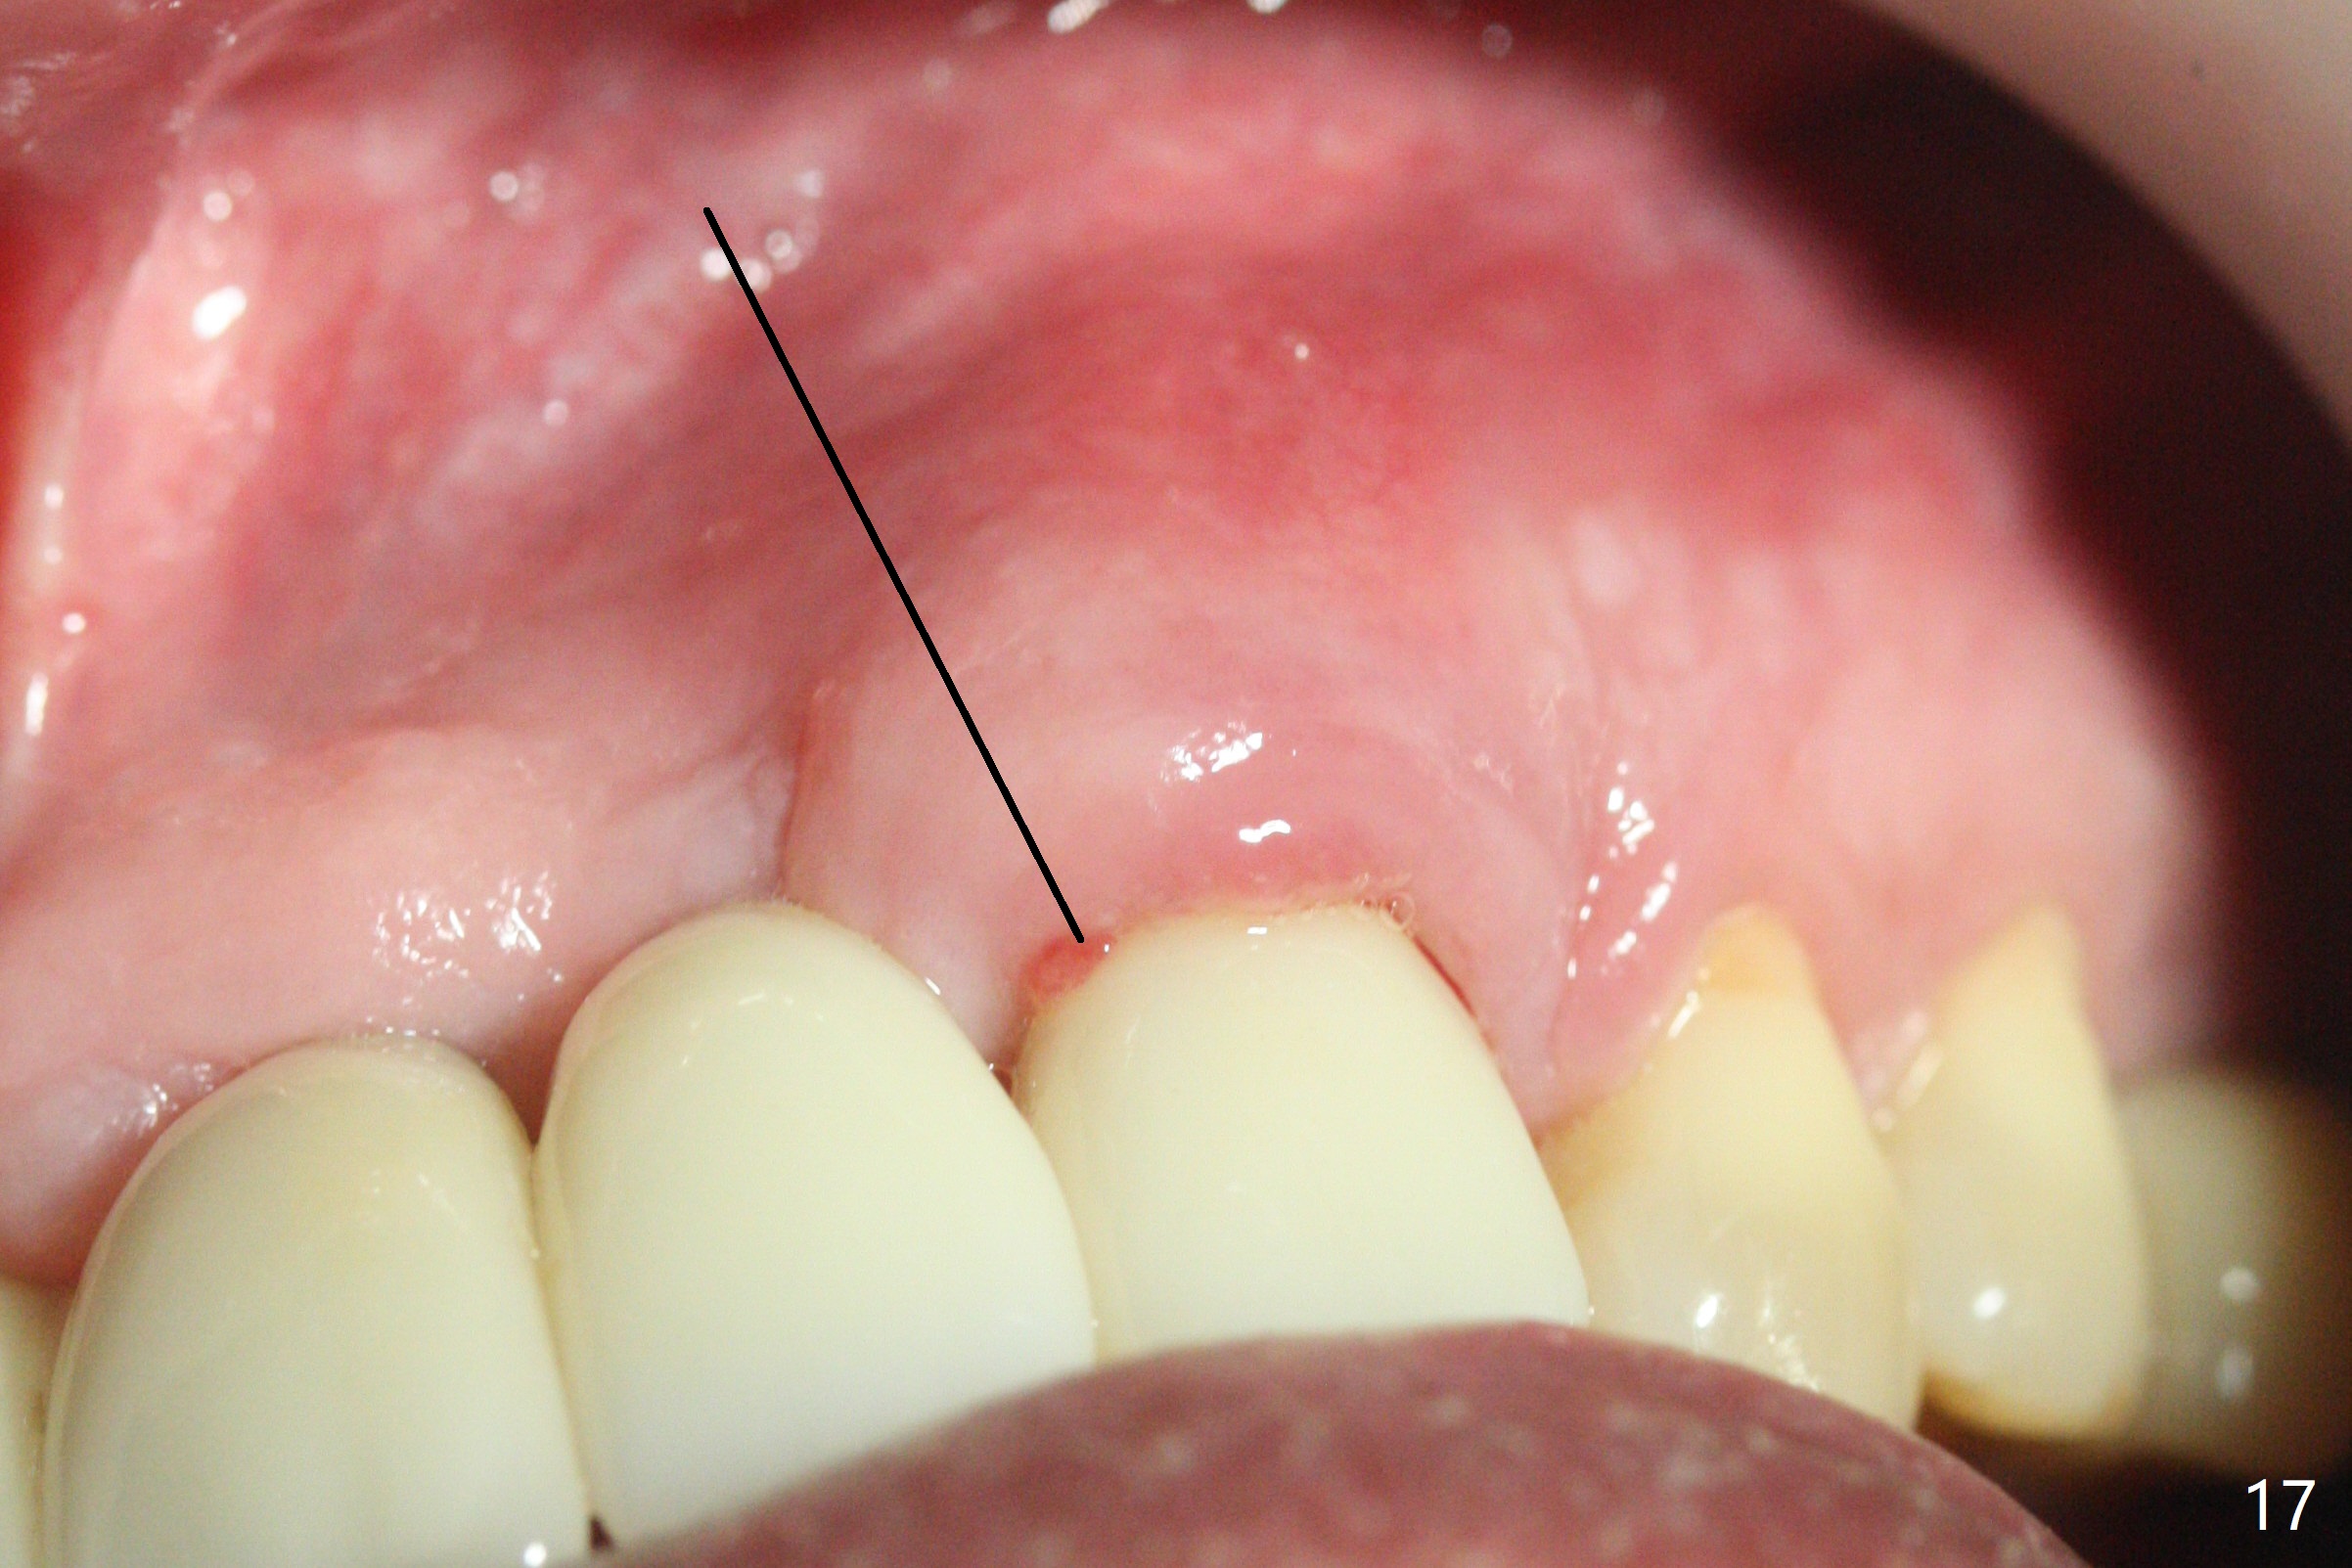

The buccal plate at #10 undergoes atrophy 9 months post immediate implant (Fig.1 *). To prevent the same post-extraction complication at #11, a technique called socket shield is going to be adopted. The buccal portion of the root (Fig.2-6 R, half-moon shaped) remains in place while a 3.5x13 mm implant is placed in the palatal portion of the socket (>50 Ncm). In fact the root is trimmed slightly subcrestal (Fig.6 C). It is assumed that there will be no or minimal bone resorption as long as the periosteum between the buccal plate and the remaining buccal root is not disturbed after tooth removal. After placement of a 4.5x15 degrees A (2mm) angled abutment and Vanilla graft (Fig.7 *), an immediate provisional is fabricated (using a central incisor crown form for #10 because of extra wide space of #11, Fig.8). There is no buccal plate atrophy at the canine 11 days postop (Fig.9). There is smooth transition from the grafted bone to the native bone 4.5 months postop (Fig.10). The buccal plate remains non-atrophic at the canine 4.5 months postop (Fig.11,12). CT taken 1 month post cementation shows that the implants at #10 and 11 are placed somewhat lingually (Fig.13,14 L (*: socket shield)). Gingival swelling is noted (Fig.15 *) with +Bleeding On Probing (^) 8 months post cementation (at the time of #21/24 impression). It appears that the socket shield (Fig.16 S) causes infection and loss of bone graft (*). The shield will be removed with an oblique accessory incision to save the papilla between #10 and 11 (Fig.17 black line). Prepare PRF for sticky bone (x1).